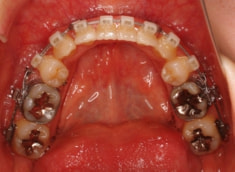

治療開始時

治療開始から約1年後

治療法:表の矯正(T21ブラケット)

ご出産のため治療中断期間あり